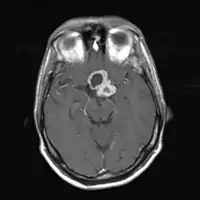

![]() Знімок МРТ головного мозку. На аксіальній томограмі визначається новоутворення з кістозним та солідним компонентами - краніофарингіома Знімок МРТ головного мозку. На аксіальній томограмі визначається новоутворення з кістозним та солідним компонентами - краніофарингіома | |

Гістопатологічна картина краніофарингіоми демонструє сквамозний епітелій, з якого формується один з гістологічних типи пухлини: адамантиномна краніофарингіома та папілярна краніофарингіома. При адамантиномній краніофарингіомі визначаються кальцифікати, що дозволяє визначати таку пухлину за допомогою МРТ.

Виконуються комп'ютерна томографія або МРТ головного мозку, завдяки яким можна визначити краніофарингіому.